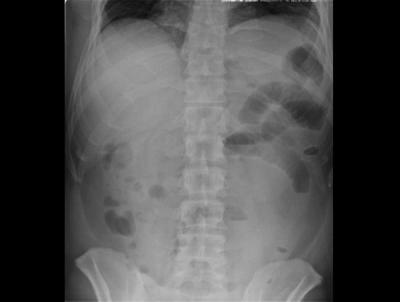

小腸にたどり着くと食後十数時間~数日後に腹痛が起こります。腸がひどくむくんでしまうと、内容物の通過が悪くなって腸閉塞を起こし、吐き気や嘔吐、下痢などをきたします。診断は、胃の場合と違ってカメラで虫体を確認することができないため、数日以内に鮮魚を生食したという食事歴と症状、CT等の画像所見から総合的に判断します。ほとんどは絶食と点滴輸液で症状はよくなりますが、まれに外科手術が必要になる場合もあります。

腸アニサキス症の場合は胃アニサキスのように簡単にはいかず、虫体の確認が困難で、腹部レントゲン写真を撮影し、小腸ガス、腹部超音波検査で腹水の確認、問診などを総合判断して診断されるそうです。極まれに、大腸内視鏡検査でアニサキス虫体を確認できることもあるそうです。

腸アニサキス症では、アニサキスが死滅し症状の緩和を待つ対症療法を行い、腸閉塞を起こした場合には外科的処置を行います。